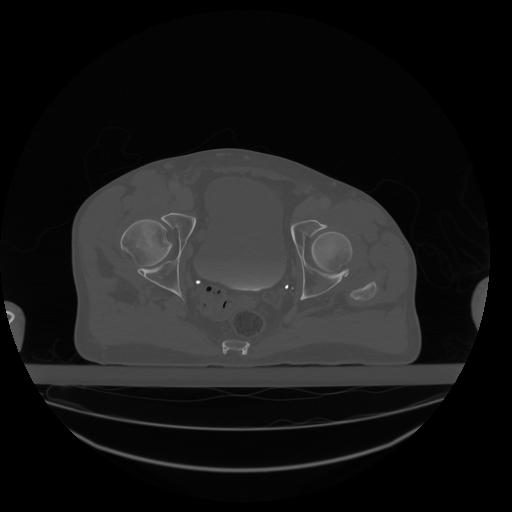

34 CUERPO,CE,Vol,1.0,CUERPO,,